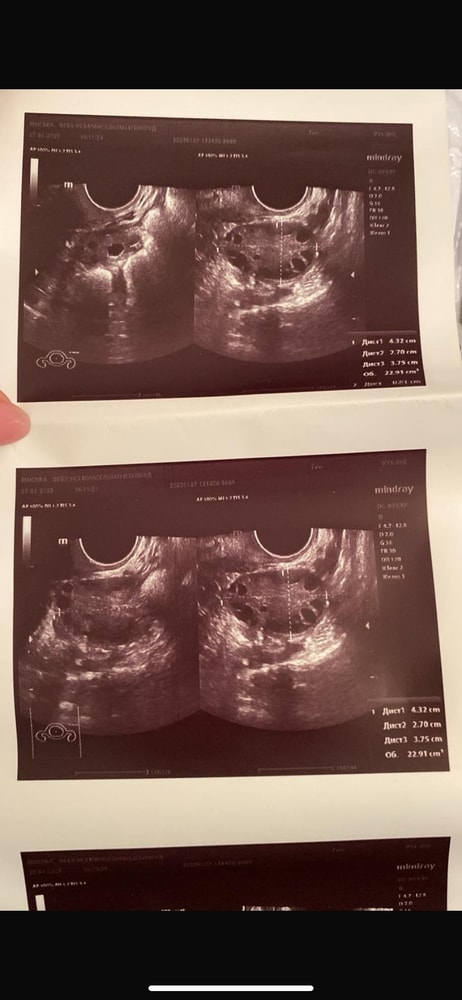

faith, делали эхо гсг и написали что там Изображение Изображение Изображение Изображение